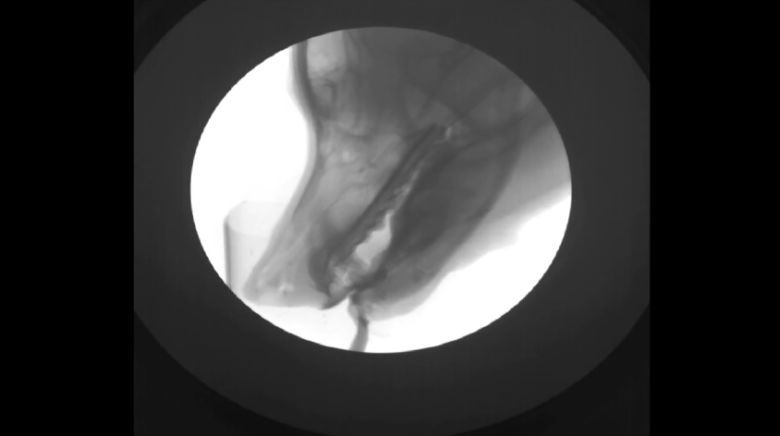

Jak pije pies na zdjęciach rentgenowskich (wideo)